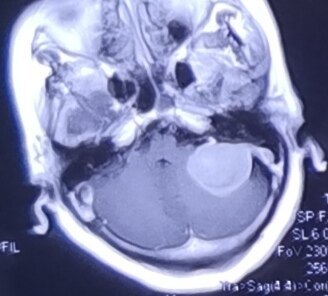

今天上午接診一位相熟的大姐介紹來的病人,因為沒有預約,我便讓病人按順序排隊等候,中間這位大姐還特意從珠海打電話給我,想我快點給她的熟人看,我還是婉轉地告訴大姐:必須按規(guī)定辦事,否則就診的秩序就會打亂,她也很理解地放下了電話。?看到這位病人時已將近中午十二點?;颊呤且晃恢心陭D女,主訴是最近幾個月來出現(xiàn)左側面部“抽搐”,病人還很清楚地告訴我,這種抽搐大多發(fā)生在半夜熟睡的時候,發(fā)作時病人便會因為難受而醒來,我特意問她有沒有疼痛的感覺,病人明確表示沒有,只是告訴我,這種抽搐的感覺是左側臉部“發(fā)緊樣的”難受。偶爾也會白天發(fā)生,白天發(fā)作時,她便會感覺到左眼也會因為抽搐而不由自主地閉合起來。體查沒有發(fā)現(xiàn)相關的神經(jīng)系統(tǒng)體征,但經(jīng)驗告訴我,當一種不適令病人在熟睡中醒來而且頻繁發(fā)生的時候,這種不適的背后一定隱藏著某種我們暫時未知的病因。盡管沒有發(fā)現(xiàn)指向性很強的體征,但這癥狀提醒我:警惕!警惕這背后隱藏的“妖怪”!我毫不猶豫地建議病人去做頭部核磁共振檢查,我的知識和經(jīng)驗告訴我,這種臉部的癥狀的病變的部位很可能就在顱內(nèi),而且其位置應該很接近面神經(jīng)。下午醒來打開手機,遠在珠海的那位大姐的電話便打了過來,說這位病人的結果已經(jīng)出來,報告說是腫瘤,正在不知所措中。我便讓她將結果拍下來通過微信發(fā)給我。?結果很快便發(fā)到我的微信上。頭部核磁共振檢查可清晰地看見,患者的左側橋腦小腦角上有一個腫物,檢查的醫(yī)生還很負責任地為她做了增強檢查,最后給出了“腦膜瘤可能性大”的診斷??赐杲Y果,我馬上建議她到神經(jīng)外科就診做進一步的治療。行醫(yī)近四十年,我很清楚,門診對一位醫(yī)生的考驗是很苛刻和嚴格的。要利用這短時間對病人的接觸來做出最為合理的判斷并根據(jù)判斷做出相應的處理,需要高度集中的注意力、豐富的臨床經(jīng)驗、深厚的專業(yè)功底、細致入微的診查,缺一不可。稍有不慎,便會出現(xiàn)誤診誤治。正因為如此,我常說:在門診坐診時,醫(yī)生腳下的薄冰更薄,更加接近深不可測的深淵,其戰(zhàn)戰(zhàn)兢兢之狀更甚。也只有我自己才知道和明白,為了第二天的門診,頭一天晚上我必須服下足夠量的安眠藥以保證睡眠的質量,從而保證第二天坐門診時有充足的精神。是的,詳細的問診和體查,關注每一個細節(jié),警惕各種反常的表現(xiàn),才有可能在各種疾病的千變?nèi)f化的癥狀中找出隱藏的“妖怪”并將其“繩之以法”!